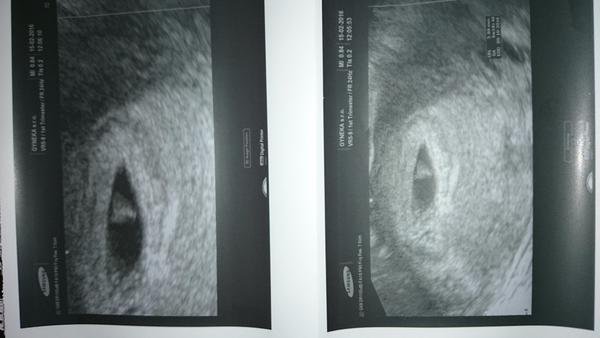

aj ja chceeem taku bublinkuuuuu.

@alexslovakia krasna

@zuzsat ďakujeme neboj aj vy budete mať strašne vám to prajem lebo je to nádhera čo prežívame aj keď sme potrebovali pomôcť. Som vďačná že niekto vymyslel iui a dal nádej že je tu možnosť pomôcť párom ktoré majú problémy. Ja veľmi ďakujem môjmu lekárovi, splnil nám sen